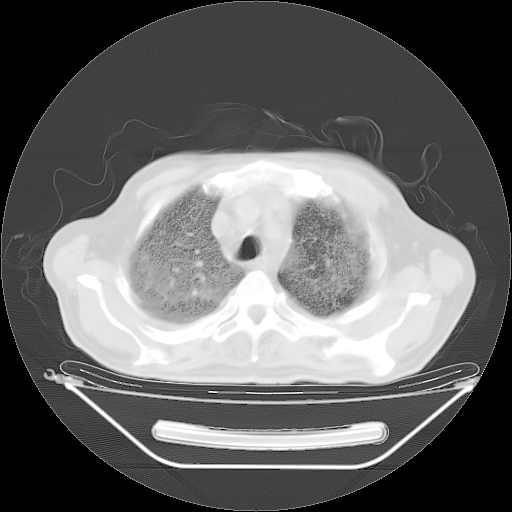

今天复查肺部CT,发现双肺广泛磨玻璃样改变。所以我把3月19日和5月9日相隔50天的肺部CT上传。请大家会诊。

2009年3月19日肺部CT片。

5月9日肺部CT(在4月27日齐鲁医院肺部CT描述部分肺组织磨玻璃样改变,12天后肺组织广泛磨玻璃样改变)

大致读了系列胸部CT:纵隔窗无明显异常,肺窗:从4、27至今:主要是双肺中下野外带可见毛玻璃样改变,目前处于急性肺泡炎阶段,至于原因考虑1、结替组织或胶原血管性疾病所致?2、恶性疾病如恶组在肺部所致的表现或细支气管肺泡癌?3、药物或其它原因如肺蛋白沉着症所致肺泡炎目前不太可能?总之,明天就去请我院的呼吸科、感染科、血液科和临免专家会诊哈。